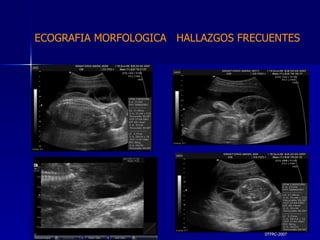

DTFRC-2007 ECOGRAFIA MORFOLOGICA  HALLAZGOS FRECUENTES   MATERIAL Y METODO ES UN ESTUDIO DESCRIPTIVO, RETROSPECTIVO  DE ESTUDIO ECOGRA FICOS REALIZADOS ENTRE MARZO 07 A MARZO 08 EQUIPO DE ALTA RESOLUCION   VOLUSON 730 PRO  MEDISON SA 8000 live MEDISON SA 8000SE CRITERIO DE INCLUSION:   POBLACION GENERAL    GESTACIONES  20 a 24 SEMANAS   UNIVERSO  N 211

DTFRC-2007 ECOGRAFIA MORFOLOGICA  HALLAZGOS FRECUENTES   Sistema Nervioso Central  8  Cardiovascular  0 Genitourinario  6 Musculos Esqueleticos  2 Gastrointestinales  2  Otros  12  Total  30   NUMEROS DE ANOMALIAS POR SISTEMA n N  211

DTFRC-2007 ECOGRAFIA MORFOLOGICA  HALLAZGOS FRECUENTES   SISTEMA NERVIOSO CENTRAL TOTAL  8  26 % 1 HIDROCEFALIA 2 VENTRICULO MEGALIA 4 QUISTE DE PLEXO COROIDEO 1 ANENCEFALIA

DTFRC-2007 ECOGRAFIA MORFOLOGICA  HALLAZGOS FRECUENTES   GENITOURINARIA DISPLASIA RENAL MULTIQUISTICA  3 HIDRONEFROSIS  2 QUISTE DE OVARIO FETAL  1 SISTEMA DIGESTIVO DILATACION INTESTINAL  2  SISTEMA ESQUELETICO   PIE BOT  2  20 % 6 % 6 %

DTFRC-2007 ECOGRAFIA MORFOLOGICA  HALLAZGOS FRECUENTES   OTROS HIGROMA QUISTICO  2 ENFERMEDAD ADENOMATOSA PULMONAR  1 ARTERIA UMBILICAL UNICA  2 HIDROPS FETAL NO INMUNE  1 QUISTE DE CORDON UMBILICAL  1 ALTERACION DE LIQUIDO ANMIOTICO  2 SINDROME TRAFUSIONAL FETO FETAL 1 LABIO LEPORINO  2 TOTAL  12  42 %